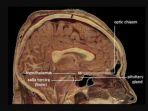

Hipotalamus

Hipotalamus adalah bagian otak yang terletak di bawah talamus membentuk lantai ventrikel